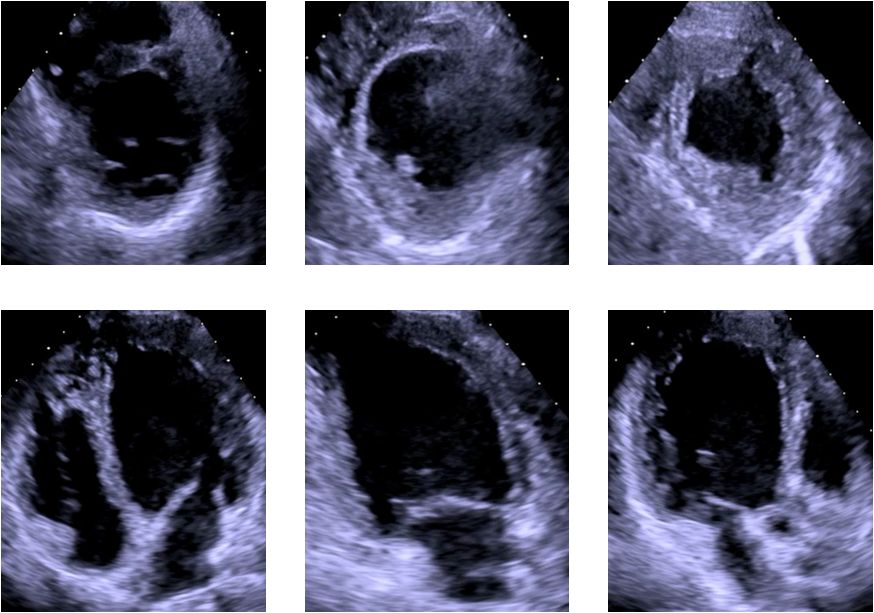

▶▷ 2018年10月29日-31岁男性,心力衰竭入院